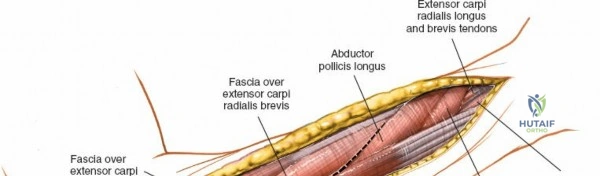

Superficial Surgical Dissection and Internervous Plane

Incise the deep fascia of the forearm in line with the skin incision. The initial goal is to identify the medial border of the brachioradialis as it courses down the forearm. It is a common pitfall to search for this border too far laterally. At the level of the elbow, the brachioradialis is expansive and extends almost halfway across the anterior forearm. It is surprisingly easy to mistake the plane between the brachioradialis and the extensor carpi radialis longus for the correct intermuscular plane.

To confirm the correct plane, look for the superficial branch of the radial nerve. This sensory nerve runs on the undersurface of the brachioradialis muscle. Once the true medial edge of the brachioradialis is found, develop the plane between it and the pronator teres (proximally) or the flexor carpi radialis (distally). Retract the brachioradialis laterally, taking care to keep the superficial radial nerve attached to its undersurface to protect it from traction injury.

The proximal radius is draped by the supinator muscle. The PIN passes directly through the belly of the supinator. To protect the nerve, the forearm must be fully supinated. Supination dynamically rotates the radius, carrying the insertion of the supinator anteriorly and simultaneously displacing the PIN laterally and posteriorly, safely away from the surgical field.

With the forearm fully supinated, identify the broad insertion of the supinator on the anterior aspect of the radius. Incise the supinator directly along the line of its insertion onto the bone. It is critical to detach the muscle by dividing its insertion sharply at the bone, rather than splitting the muscle belly, which would risk cutting the PIN.

Proceed with strict subperiosteal dissection, elevating the supinator laterally off the bone. This is one of the rare instances in orthopedic surgery where the safety gained by staying in a subperiosteal plane completely outweighs the theoretical vascular damage to the bone caused by periosteal stripping. The elevated supinator muscle belly now acts as a protective cushion for the PIN.